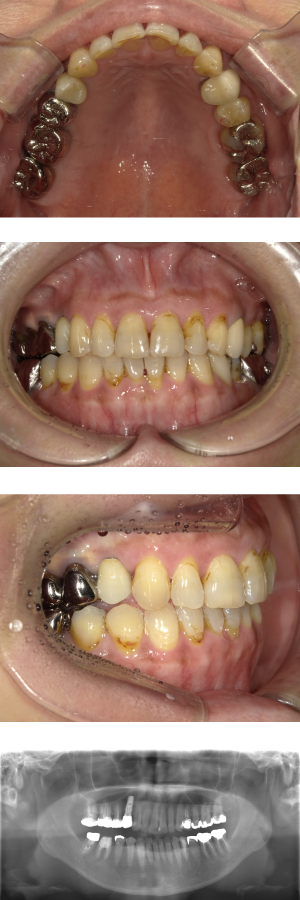

30代 女性 インプラント治療(鎮静療法)

| 年代・性別 | 30代・女性 |

| 主訴 | 口腔内かなり状態悪く、これから先しっかり噛んで食事ができるようにインプラントを入れたい。 |

| 部位 | 左上3,5,7、右下5 |

| 治療期間 | 約11ヶ月 |

| 費用 | ¥2,145,000(税込) |

| 副作用・リスク |

|